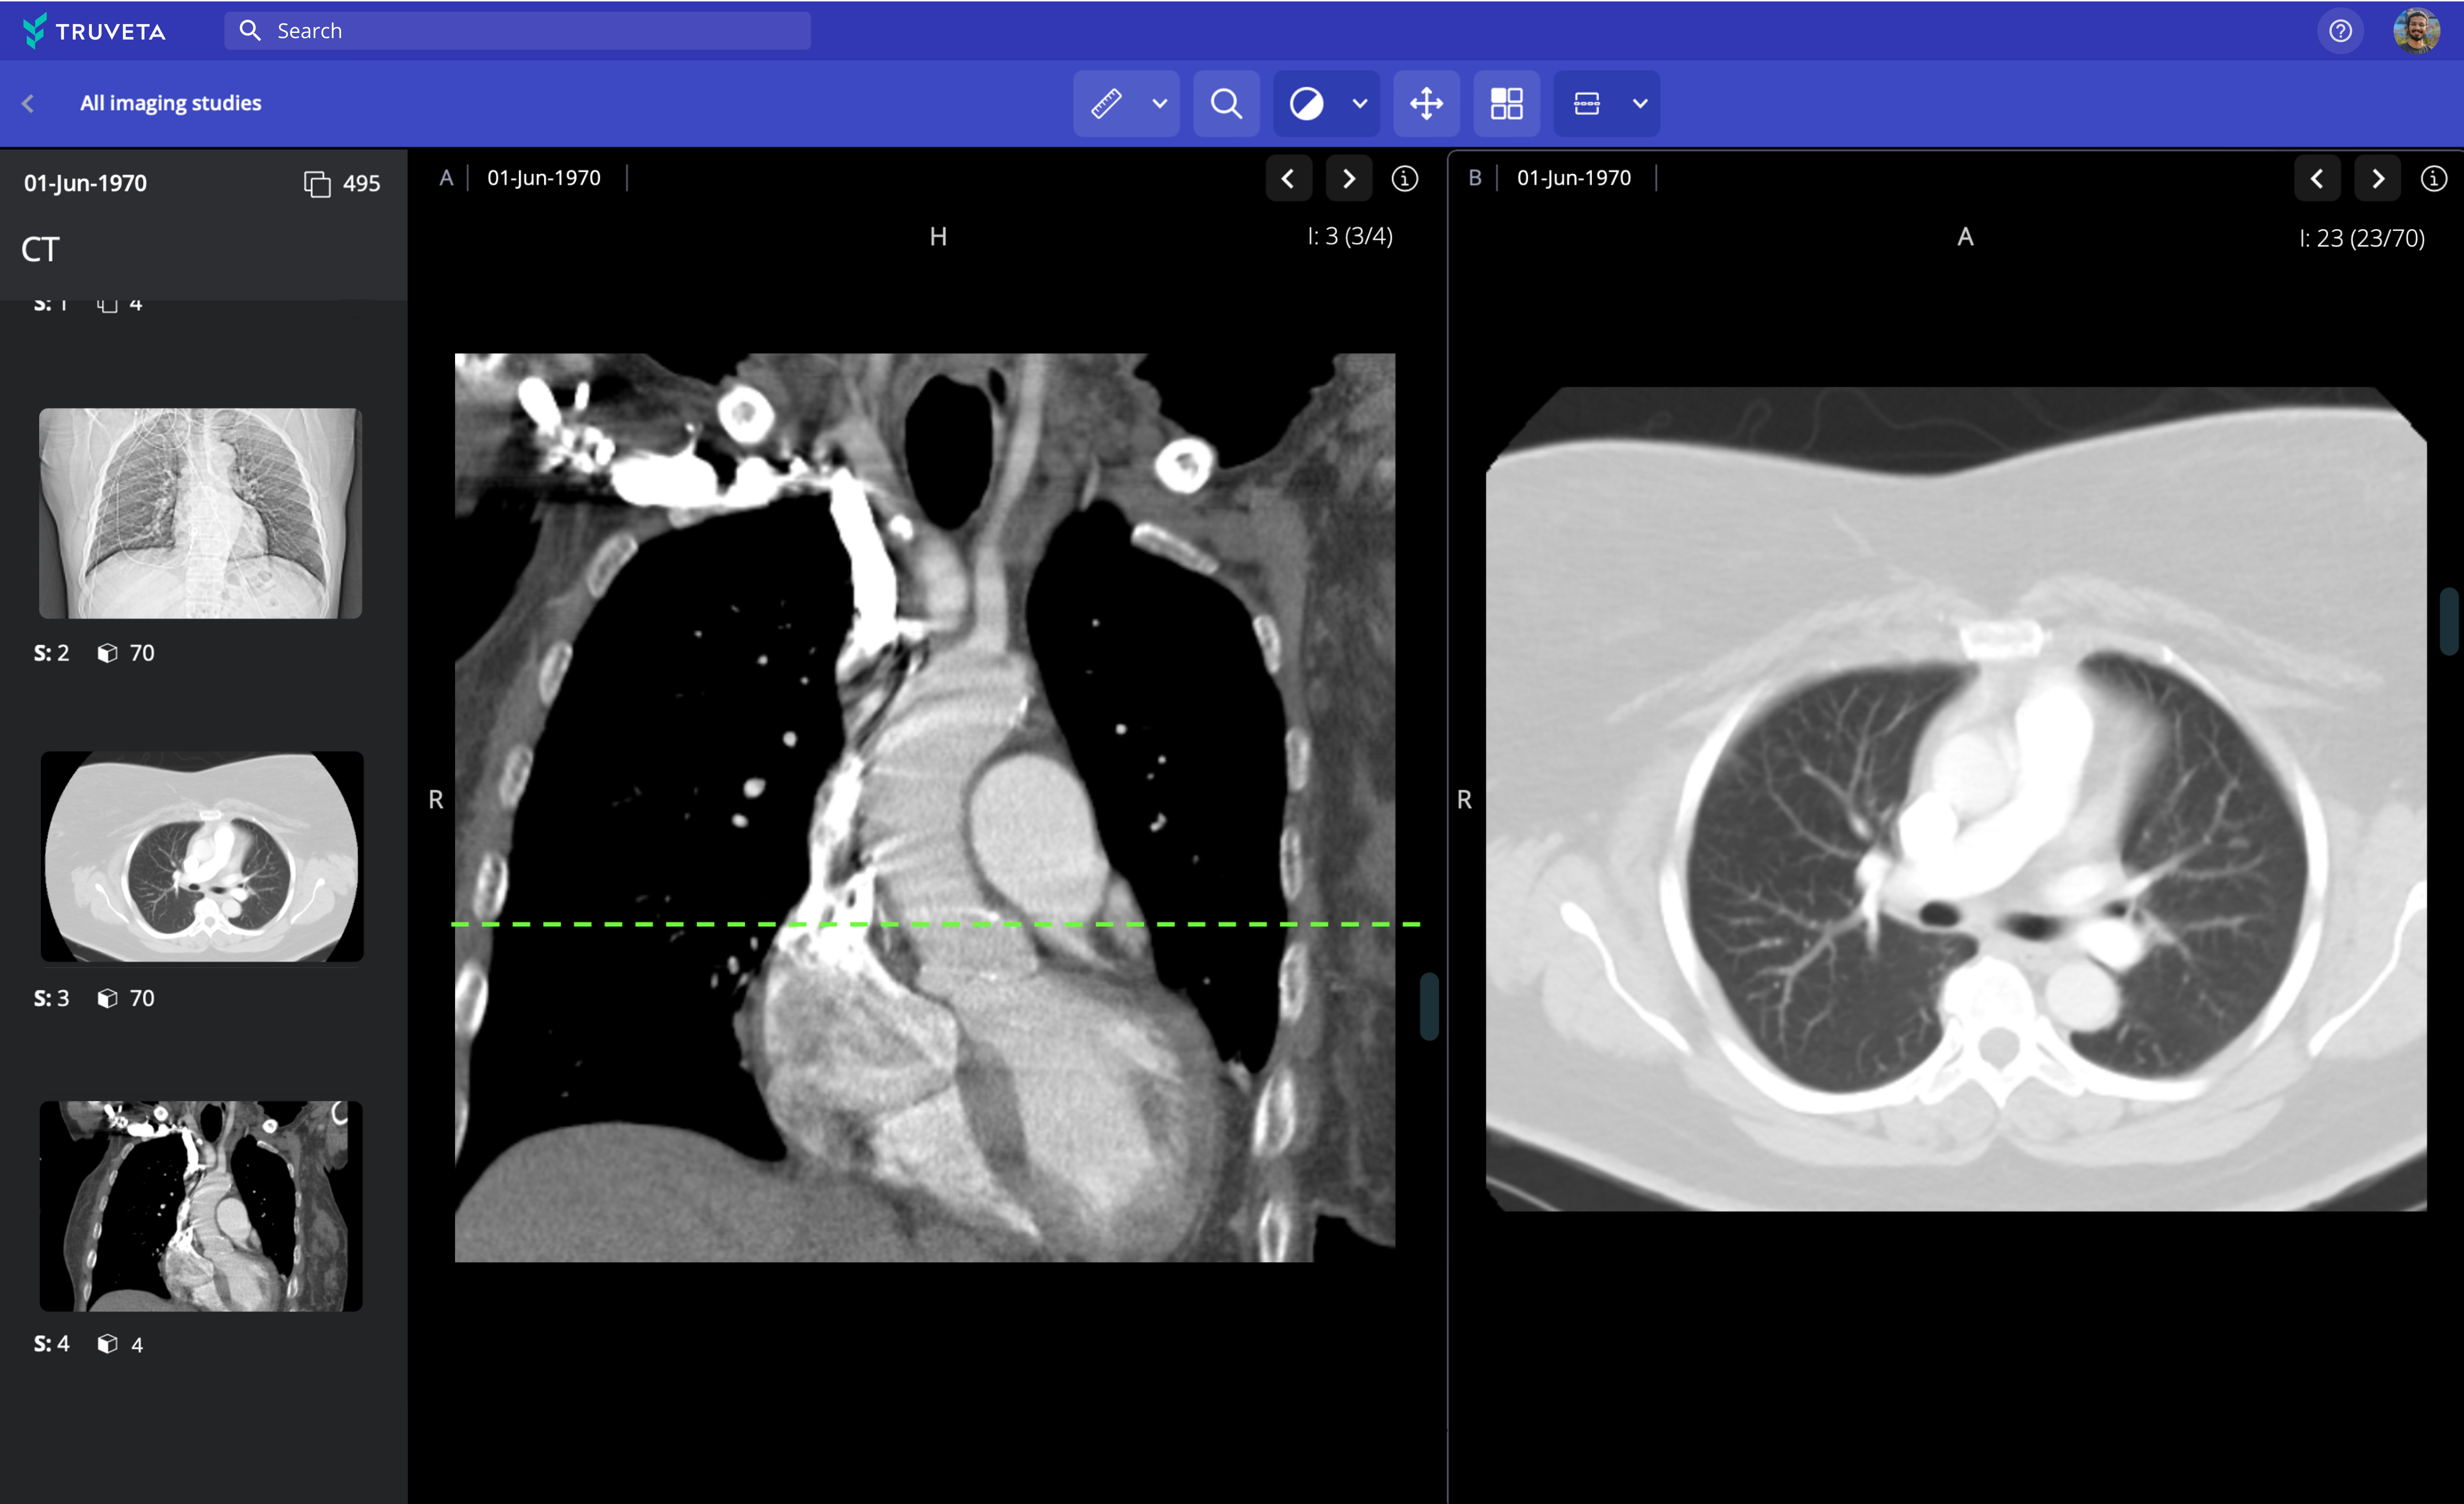

Explore images across modalities and therapeutic areas

Truveta provides pixel data and imaging metadata including MRI, CT, X-ray, ultrasound, mammogram, PET, and nuclear medicine, searchable by modality and protocol.

Lung CT

Lung CT metadata

Truveta provides pixel data and imaging metadata including MRI, CT, X-ray, ultrasound, mammogram, PET, and nuclear medicine, searchable by modality and protocol.

Lung CT metadata

Complete metadata is included with each image, including size, dimensions, bit depth, modality, and equipment settings.

Accelerate research with integrated analytical tools

Truveta Studio enables researchers to preview images and easily annotate using built-in tools.

De-identified images can be analyzed in notebooks in Truveta Studio and exported for studying imaging-based outcomes and observations, AI/machine learning model development, or inclusion in publications.